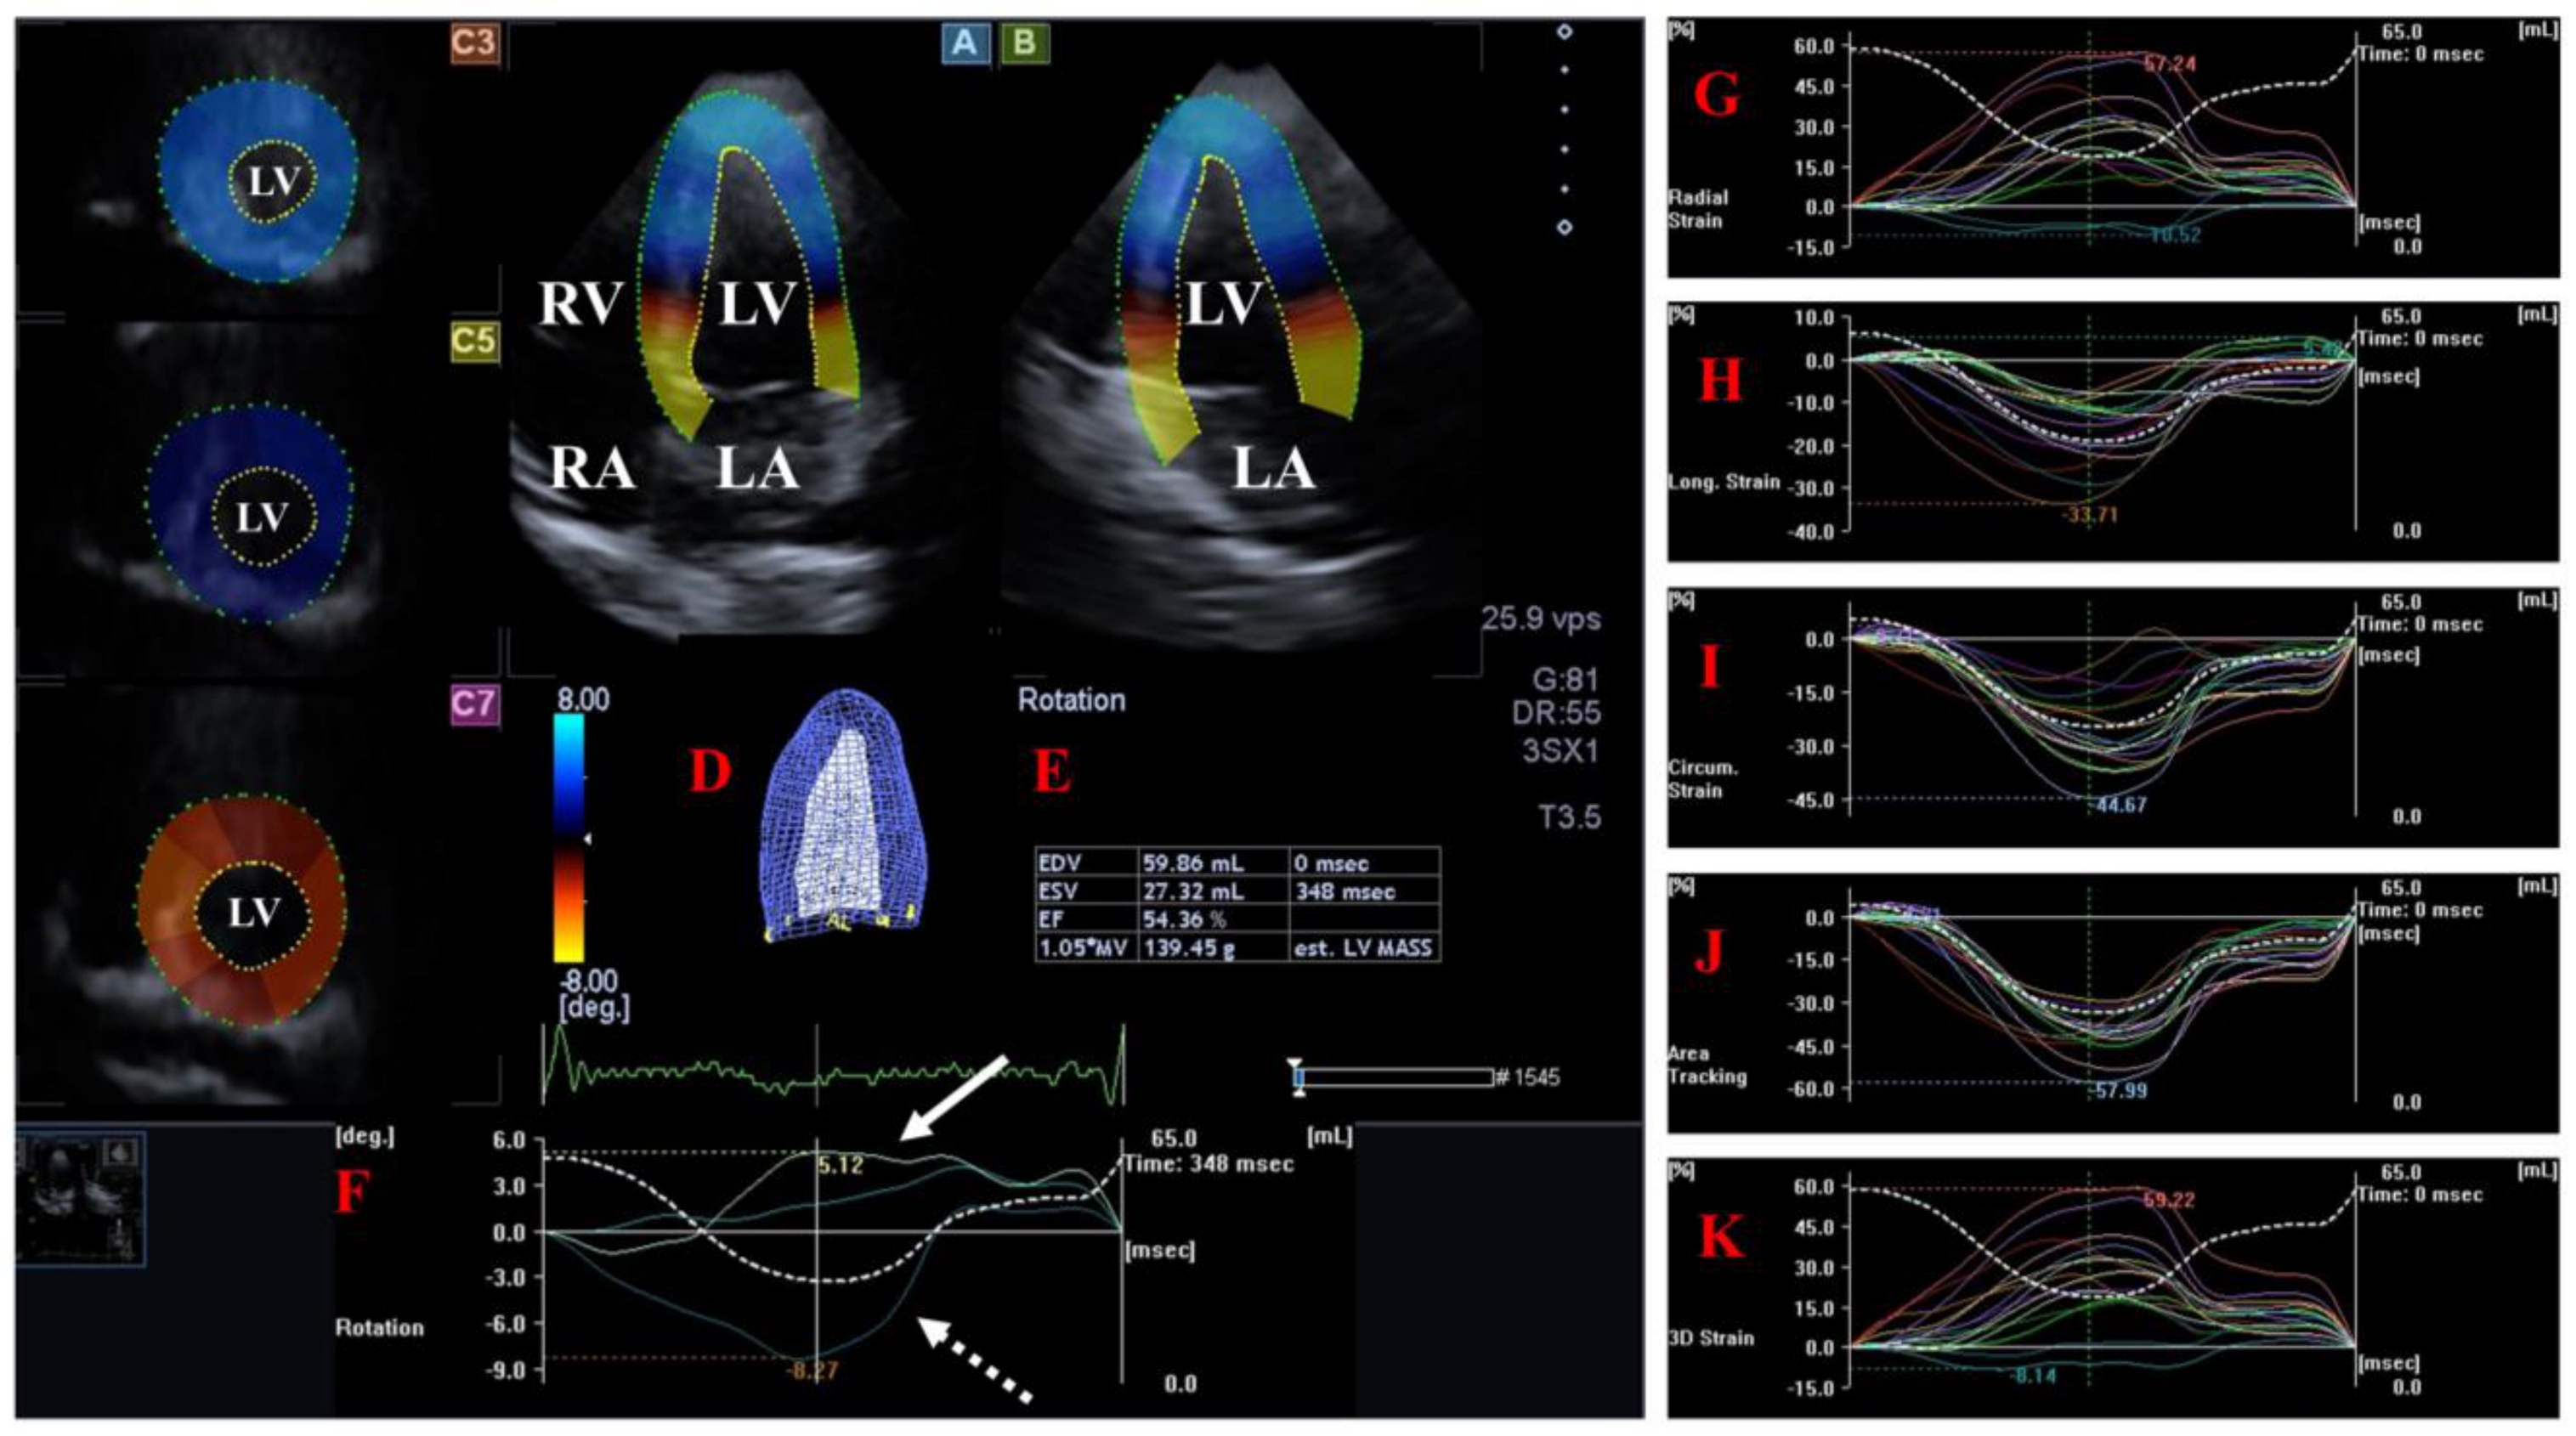

The LV is the central engine of systemic circulation. The two papillary muscles of the LV are required for the proper function of the mitral valve (MV) separating the LV and the left atrium (LA) and allowing blood flow from the LA into the LV during diastole. The blood leaves the LV via the aortic valve (AV), which prevents the backflow of blood from the aorta to the LV during diastole under healthy circumstances. The fibers in the subepicardium are left-handed, the mid-layer fibers run in the circumferential direction, while the fibers in the subendocardium are right-handed [16]. The LV moves in a 3D pattern including radial, circumferential and longitudinal deformation. This sort of movement can be characterized by several quantitative parameters named echocardiographic (unidirectional strains represented by its 3D motion: radial (LV-RS), longitudinal (LV-LS) and circumferential (LV-CS). While area (LV-AS) strain combines LS and CS, 3D (LV-3DS) strain combines all unidirectional strains [5,6,7,8,17,18,19,20]. In addition to the above, LV has a movement similar to wringing a towel called LV twist. In this case, the LV base rotates in a clockwise direction, while the LV apex rotates in a counterclockwise direction in systole [17,18,19] [Figure 1].

Figure 1.

Examination of the left ventricle (LV) by three-dimensional (3D) speckle-tracking echocardiography. Following echocardiographic data acquisitions, the following typical views are created: (A) Apical 4-chamber and (B) two-chamber longitudinal views and (C3,C5,C7) cross-sectional views at apical, midventricular and basal levels, respectively. LV can be easily detected alongside other heart cavities including the left atrium (LA) and the right atrium (RA) and ventricle (RV). A number of other details were also presented including (D) 3D cast and (E) end-diastolic (EDV) and end-systolic (ESV) volumes of the LV together with ejection fraction (EF) and mass of the LV and (F) curves representing changes in volumes and strains of LV over time. (F) Apical [white arrow] and basal [white dashed arrow] LV rotations and (G) radial, (H) longitudinal, (I) circumferential, (J) area and (K) 3D strains are also demonstrated.